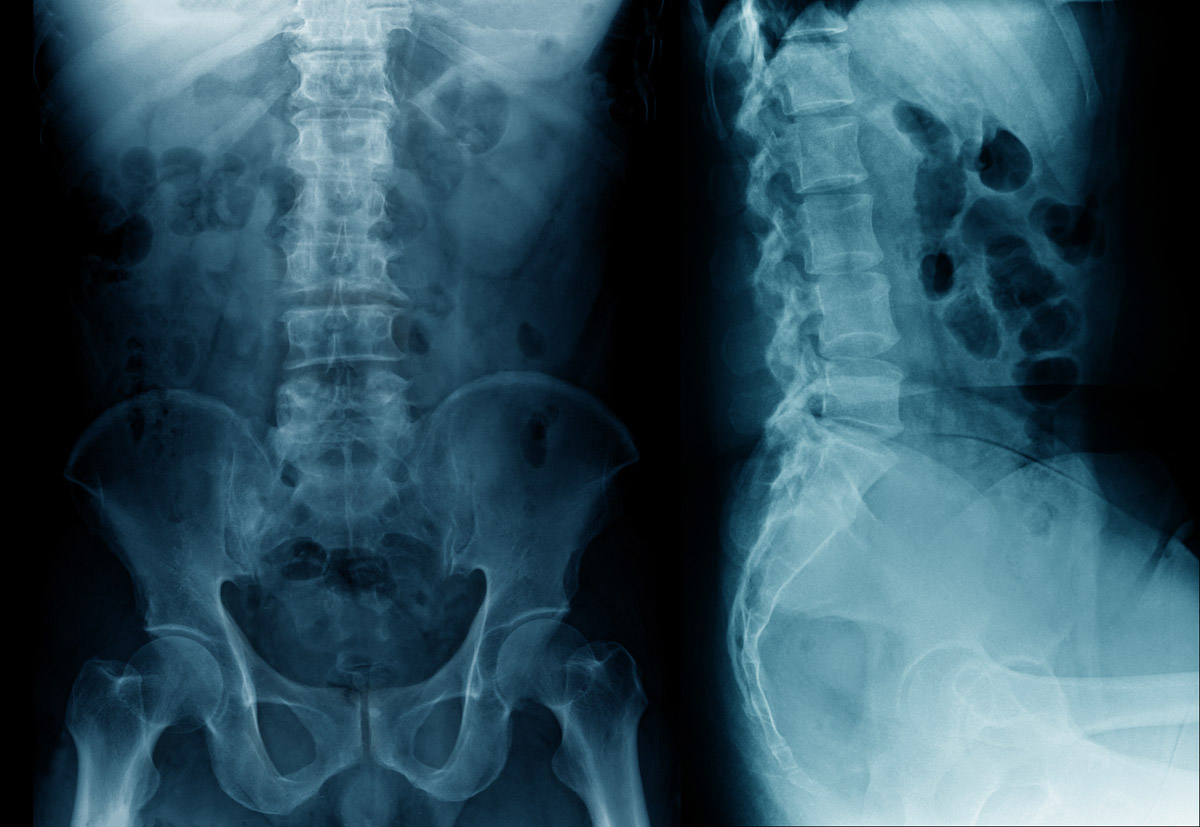

5. назначит рентгенологическое исследование и магниторезонансную томографию таза;

Рентгенограмма покажет деформацию копчиковых костей, расположение осколков. Магниторезонансная томография выявит повреждение мягких тканей костными обломками. Ректальное и влагалищное обследование поможет узнать, в каком направлении сместились обломки копчика. Таким образом, комплексное обследование позволяет составить реальную полную клиническую картину: определить характер травмы, оценить уровень осложнений, вызванных ею. На основании его результатов, назначается уже соответствующее лечение.

Травматическая деформация копчика может проявляться в разных формах. Например, при вывихах смещаются отдельные элементы, теряется их конгруэнтность. При переломах же происходит отлом сегментов либо крайнего позвонка. Обломки могут смещаться и повреждать мягкие ткани, нервные волокна, мышцы. Чтобы выявить все симптомы перелома копчика и последствия этой травмы, нужно провести комплексное обследование больного. Оно включает в себя:

• рентгенологическое исследование (точность выявления деформаций костей достигает 97 %, стоимость процедуры в столице — от 1200 руб.);

• компьютерная томография копчиковой зоны (точность диагностики 99 %, стоимость процедуры в Москве от 3800 руб.);

• магниторезонансная томография копчика (точность процедуры 99 %, цена в столичных клиниках от 2700 до 4000 руб.).

Рентгенологическое исследование проводится в нескольких проекциях и в различных положениях корпуса пациента. С его помощью удается определить линию разлома кости. Компьютерная и магниторезонансная томография позволяют детализировать картину. Ведь тонкие копчиковые косточки и возможные обломки скрыты под толщей мягких тканей, потому не всегда хорошо просматриваются на рентгенограмме.